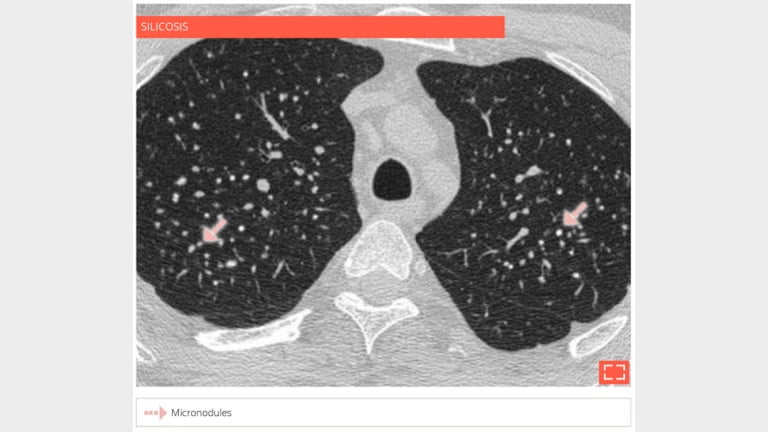

1. Micronodulation, perilymphatic distribution

perilpaticdistribution

• Coal workers’ pneumoconiosis.

• Extensive micronodulation with a perilymphatic distribution. Micronodules have an apical and posterior predominance.